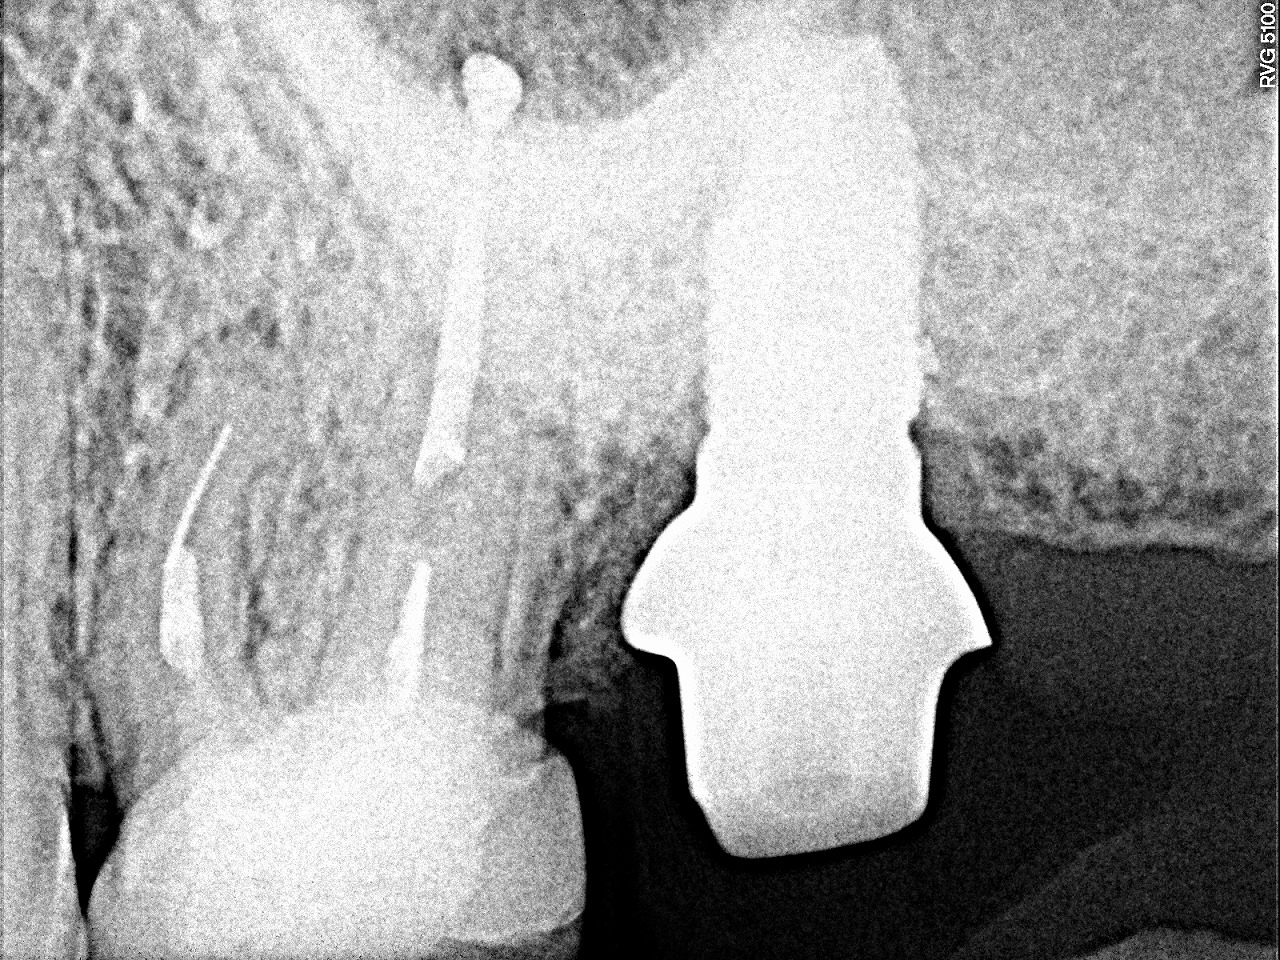

最終補綴になります

最終補綴に5mmの13mmというインプラントを埋入しています